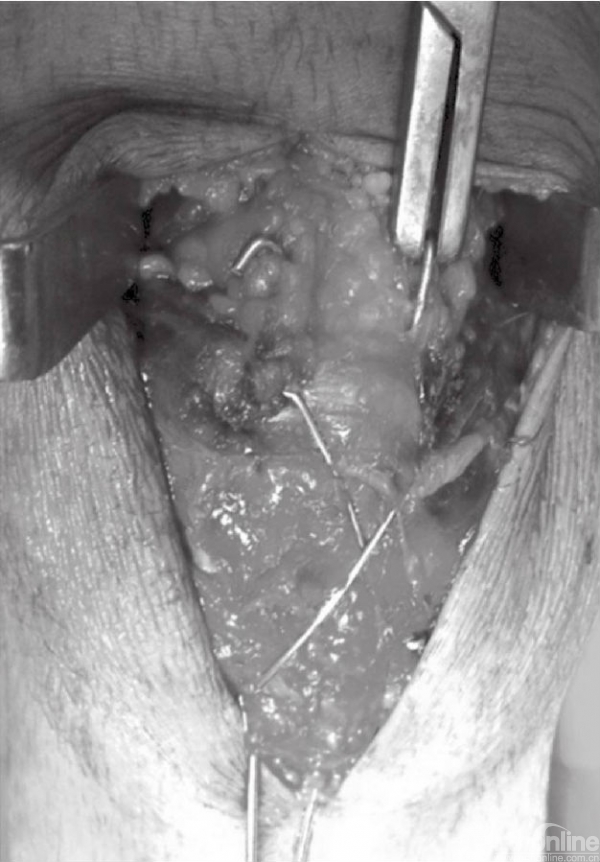

应仔细探查关节,以辨识游离骨块以及关节面损伤(图6)。此时,可对骨折进行复位,并以复位钳进行临时固定。检查骨折复位情况以及关节稳定性,关节内骨块的解剖复位是非常重要的。术中复位困难,可能是因为小骨块或者软组织嵌于骨折端。

图6 应仔细探查关节以辨识游离骨块以及关节面损伤